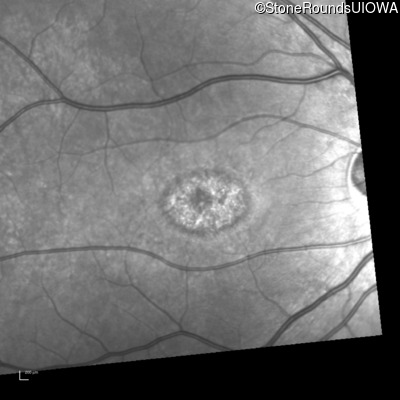

Infrared Fundus Photograph - Right - 20/50 -1

Exemplar

Infrared Fundus Photograph - Right - 20/40 -2